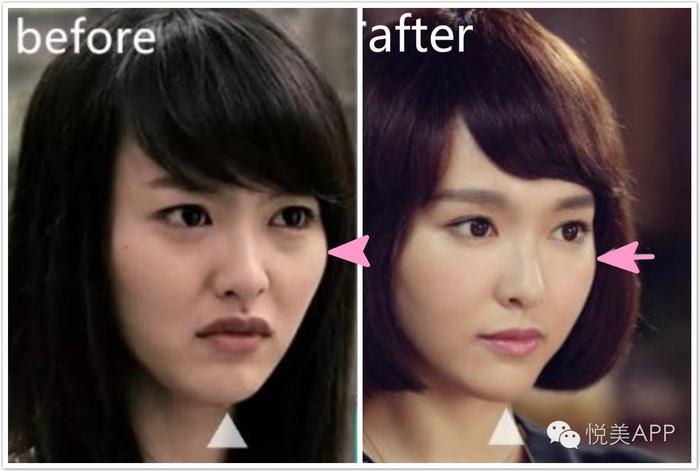

就像早期的大幂幂

做完这几步,就能像唐唐这样,

颧骨变小了,但脸还是紧绷绷

颧骨手术是个魔术,把人变成4000年美女

把人瞬间变年轻

大饼脸变巴掌脸